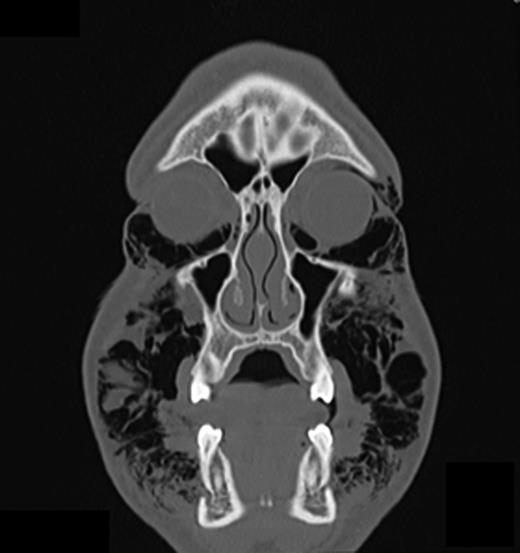

Computed tomography (CT) of the head and neck region revealed a bilaterally located subcutaneous air collection in the area of the periorbital, temporal, paramandibular and supraclavicular region (Figs 3–5). There were no signs or symptoms of severe complications such as pneumothorax or pneumomediastinum.

The frontal CT scan of the head and neck region (section in the retromolar region) illustrates bilaterally trapped air into the soft tissue reaching from the temporal fascia through to the supraclavicular region.